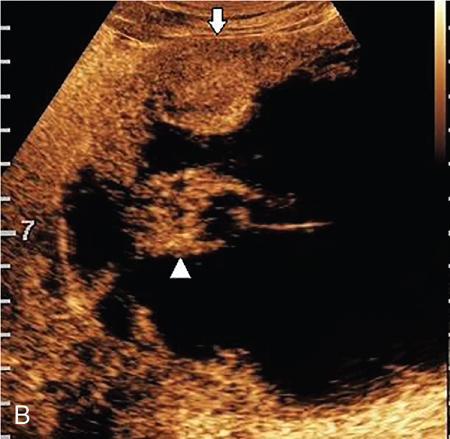

Drushi Patel CONTRAST-ENHANCED ULTRASOUND IN ADULT GENITOURINARY IMAGING Mridula Muthe Ultrasound is the initial screening examination for the evaluation of the renal morphology and suspected renal lesions due to its multiple advantages such as easy accessibility, bedside assessment, affordability and lack of radiation. Vascularity of the kidney and renal lesions can be studied with the use of colour Doppler ultrasound however, it provides information only about the macrovasculature. With the use of microbubble ultrasound contrast agents (UCAs) macro as well as the microvasculature can be studied. Contrast-enhanced ultrasonography (CEUS) is also more sensitive than Doppler ultrasound as it is not affected by blood velocity and angle of insonation of the ultrasound beam. In urology, the established applications of CEUS in adults include characterization of cystic lesions and differentiation between pseudotumours and solid lesions. Box 10.23.1.1 provides a list of European Federation of Societies for Ultrasound in Medicine and Biology (EFSUMB) recommended indications of CEUS in renal evaluation. EUROPEAN FEDERATION OF SOCIETIES FOR ULTRASOUND IN MEDICINE AND BIOLOGY (EFSUMB) RECOMMENDED INDICATIONS FOR USE OF UCA IN RENAL EVALUATION Renal ischaemia. Evaluation of solid renal lesions. Differentiation between solid renal lesions and pseudotumours. Characterization of complex cystic masses. Characterisation of indeterminate renal masses. Renal infections. Follow-up of nonsurgical complex masses. To improve lesion visualization in patients undergoing renal tumour ablation under US guidance and to detect residual tumour either immediately or after ablation. Isolated blunt moderate-energy renal trauma. Follow-up of trauma patients managed conservatively. Characterization of thrombus in renal vein and inferior vena cava. In patients with contraindications for CT- and MRI-based contrast media. Evaluation of lesions in transplant kidneys. Evaluation of ischaemia and vascular complications in transplant kidneys. Tumour response assessment to biologic therapy. Intracavitary CEUS for guiding percutaneous nephrostomy. Source: P.S. Sidhu, V. Cantisani, C.F. Dietrich, O.H. Gilja, A. Saftoiu, E. Bartels, et al., The EFSUMB guidelines and recommendations for the clinical practice of contrast-enhanced ultrasound (CEUS) in non-hepatic applications: update 2017 (long version). Ultraschall in der Medizin-Eur. J. Ultrasound 39 (02) (2018) e2–e44. CEUS involves the intravenous injection of UCAs consisting of gas microbubbles. These UCAs remain purely in the intravascular compartment as they are small enough to avoid filtration by the lungs and too large to enter the interstitial compartment. UCAs cause marked amplification of signals from the flowing blood, thus providing information about the microvasculature and parenchymal perfusion. Sonovue is a second-generation UCA and is the only UCA available in India. It consists of sulphur hexafluoride gas which is exhaled by the lungs and is surrounded by phospholipid monolayer which is metabolised by the liver, making it safe for patients with renal insufficiency. For renal evaluation, a dose of 1–1.5 mL of Sonovue is administered as a bolus dose followed by a 10 mL saline flush. CEUS is performed on machines with contrast-specific software’s using a low mechanical index (MI) technique. The use of a dual image display is beneficial for the evaluation of small lesions. A conventional B-mode ultrasound is first performed to acquire measurements, assess morphology and to detect focal lesions along with Doppler ultrasound to assess vasculature. However, due to limitations in the assessment of focal lesions, microvasculature, complex cysts, poor contrast between the lesion and cortex or medulla, it is preferable to perform a CEUS study for additional characterization. The enhancement pattern of the kidney is different than that of the liver due to the dual blood supply of the liver as opposed to afferent arterial supply and efferent venous drainage of the kidney. After an intravenous bolus of UCA, kidneys show intense enhancement. Contrast is first seen in the main renal artery, followed by its branches. CEUS has only two enhancement phases, that is cortical phase which lasts for 15–30 seconds and a parenchymal phase (enhancement of both cortex and medulla) for 25 seconds–4 minutes after UCA administration. The renal cortex enhances first, followed by the outer medulla which is followed by gradual enhancement of the pyramids (Fig. 10.23.1.1). During the washout phase first, there is a reduction in the medullary enhancement followed by a slower washout of the cortex. As kidneys don’t excrete UCAs, there is no opacification of the pelvicalyceal system. UCAs can act as a problem-solving tool in patients with renal failure as they are not nephrotoxic. Due to its excellent ability to depict renal vascularization, it can be used for detecting perfusion abnormalities. CEUS is useful for detecting vascular causes of renal function deterioration. Renal infarcts appear as wedge-shaped nonenhancing areas in all phases. Renal infarcts show a focal complete lack of parenchymal enhancement on CEUS whereas ischaemic areas show reduced enhancement. CEUS can confidently differentiate infarction from cortical necrosis by the demonstration of preserved hilar vascularity in the latter. Renal pseudotumours such as foetal lobulations, dromedary hump, parenchymal hypertrophy due to renal scarring and column of Bertini can be accurately differentiated from true tumours using CEUS. Pseudotumours show similar enhancement to the adjacent parenchyma and appear isoechoic on all phases while true tumours show different enhancement pattern on at least one phase (Fig. 10.23.1.2). True tumours will cause mass effect and distort the normal vascular architecture of the renal parenchyma whereas in pseudotumours the vascular architecture is preserved. In addition, the identification of medullary pyramids within the mass points towards it being a pseudotumour rather than a true mass. Cysts can be categorized according to the Bosniak classification using CEUS. Due to its superior spatial and temporal resolution, CEUS is considered superior to CT for detecting additional septations, wall or septal thickening and solid components (Figs 10.23.1.3–10.23.1.5). CEUS allows for real-time imaging of blood flow within the septae, wall or nodules within the cysts which may not be seen on CT or MR imaging. The sensitivity of CEUS is comparable to CT for the classification of renal cystic lesions as benign or malignant however, it is not as useful for staging. The follow-up of inoperable complex cystic lesions is better performed with CEUS rather than CT due to the absence of ionizing radiation. Complex cysts or masses with calcifications are not suitable for evaluation with CEUS. CEUS allows a detailed evaluation of the circulation in mass lesions as it demonstrates the macro as well as microvascular enhancement patterns. CEUS has more sensitivity than CT for detecting blood flow in hypovascular lesions. It can also be used to distinguish between complex cysts and solid lesions which remain equivocal on CT and ultrasound (B-mode and colour Doppler). CEUS is sensitive in identifying cystic areas, necrosis, debris and haemorrhage in small tumours that may be difficult to visualize on CECT and MR. Isoechoic lesions on conventional ultrasound are better characterized by CEUS (Fig. 10.23.1.6). Hyperdense renal lesions on noncontrast CT (NCCT) with HU values between 20 and 70 are better evaluated by CEUS which can classify these lesions as solid or cystic. CEUS can suggest the histological subtype of tumours. Clear cell carcinomas show heterogeneous hyperenhancement in the cortical phase and rapid washout along with a peripheral enhancing rim or pseudocapsule seen during the parenchymal phase. Papillary carcinoma shows progressive heterogeneous enhancement during the cortical phase and displays hypoenhancement as compared to the cortex on all phases. Malignant renal vein thrombus will show enhancement as compared to bland thrombus on CEUS. Tumours that are smaller than 3 cm commonly show homogeneous enhancement, regardless of their histologic subtype. Differentiation between angiomyolipoma, renal cell carcinoma and oncocytoma is not always possible. Although, CEUS has excellent sensitivity for the detection of malignancy, it has a higher false-positive rate as compared to CECT. Hence, combined use of CEUS for its high sensitivity and CECT for its high specificity may be performed for an accurate diagnosis. CEUS is effective in patients with complicated pyelonephritis, for identifying inflammatory parenchymal involvement, characterized by round or wedge-shaped hypovascular parenchymal areas, most conspicuous during the late parenchymal enhancement phase. An abscess is seen as a nonenhancing area, with or without peripheral or septal enhancement. CEUS can also be used for the follow-up of renal abscesses. All the aforementioned indications of CEUS in native kidneys also apply to renal transplants. Infarction, vascular complications such as arterial and venous thrombosis can be detected. Quantitative CEUS for assessment of graft dysfunction is a subject of active research. CEUS can be used as an alternative to CT especially in children with isolated blunt moderate energy injuries who are hemodynamically stable. It can also be used in the follow-up of conservatively managed trauma patients and in renal impairment. During Focused Assessment with Sonography for Trauma (FAST), the examination should begin with the kidneys as they have a fleeting enhancement. The kidneys are studied in the arterial phase with two separate doses administered for either kidney during FAST. On CEUS, lacerations, hematomas, and infarcts are seen as nonenhancing areas on late-phase images whereas contusions may show faint enhancement. Pseudoaneurysms and active bleeding are diagnosed on the arterial phase. Crucial complications such as devascularized parenchyma and acute cortical necrosis can also be diagnosed on CEUS. Pelvicalyceal system injury cannot be detected by CEUS as UCAs are not excreted by the kidneys. CEUS can be performed in conjunction with percutaneous ablation therapies. Preablation evaluation with CEUS is essential to assess lesion vascularity and to compare pre and postprocedure tumour viability. Also, the identification of a pseudocapsule predicts improved ablation efficacy. CEUS has demonstrated high sensitivity, specificity and accuracy for the early detection of residual unablated tumour. Dynamic contrast-enhanced ultrasound is a useful tool for early identification of responders and nonresponders, enabling tailoring of the treatment regimen. It is performed by two methods – Bolus injection of a UCA with time-intensity curve analysis (commonly used) and intravenous injection of UCA with disruption–replenishment analysis. In patients with chronic kidney disease, the contrast enhancement is less intense and fades earlier as compared to a normal kidney. CEUS aids in characterizing renal lesions in patients with renal failure. Characterization of lesions with indeterminate appearances in patients with renal dysfunction, on conventional US prevents unnecessary further evaluation with contrast-enhanced CT or MRI and further deterioration of the renal function as well as unwarranted investigations. CEUS nephrostomogram can be performed after percutaneous nephrostomography to confirm the correct positioning of its tip, detect the site of obstruction and to diagnose complications. UCAs can be safely administered in patients with minimal risk. They can be safely administered in patients with renal insufficiency as they are not excreted by the kidneys. Prior laboratory tests are not indicated as they are not nephrotoxic and don’t interact with thyroid function. Most adverse effects are mild such as nausea, headache, chest discomfort, chest pain and resolve spontaneously. The contraindications include known hypersensitivity, patients with right-to-left shunts, severe pulmonary arterial hypertension (pulmonary arterial pressure >90 mm Hg), uncontrolled systemic hypertension, and respiratory distress. The rate of anaphylactic reactions is significantly lower than iodinated contrast media and comparable to gadolinium-based contrast agents. Caution should be exercised in patients with severe acute coronary disease and in patients with unstable angina. CEUS is a rapidly evolving technique, can be conveniently performed as an extension of conventional ultrasound and acts as a valuable tool in the characterization of indeterminate renal lesions, especially when the lesion is small. The advantages of CEUS include quick assessment, real-time imaging, high contrast resolution, excellent safety profile, lack of ionizing radiation, great repeatability, and most importantly, ideal for contrast evaluation in patients with deranged renal function. DUAL-ENERGY AND SPECTRAL IMAGING IN GENITOURINARY SYSTEM Aditi Chaitanya Gujarathi-Saraf Dual-energy CT (DECT) also known as ‘spectral imaging’, was first conceptualized in the 1970s. However, the clinical applications of DECT have recently emerged as owing to improvements in postprocessing techniques. The development of a single-detector, single-source DECT (ssDECT) with the capability for rapid alternation between two peak voltage settings (‘fast switching’) and a dual-detector, dual-source DECT (dsDECT) system in last few years have made possible various applications in solving clinical problems. In DECT, the simultaneous use of two different X-ray beam energy settings (80 and 140 kVp) allows the differentiation of materials on the basis of their attenuation characteristics (material density). There are two major applications of DECT in genitourinary system. First being characterization of renal calculi to differentiate those containing uric acid (UA) from those which do not. The other application is to characterize small renal masses which include differentiating complex cysts from renal tumours, detection of solid growth in PCKD patients and detection of residual tumour after thermal ablation of a renal neoplasm. The principle of DECT imaging is based on the differential absorption of X-ray energy at variable kVp settings. In DECT, two energy levels (typically 80 and 140 kVp) are used to acquire images that can be processed to generate additional datasets. Thus, a tissue or any material in the body shows different degrees of attenuation when scanned at different X-ray energies. Conventional CT numbers (attenuation measurements in Hounsfield units) are related to the linear attenuation coefficient of a particular material. The unique linear attenuation coefficients obtained by imaging at two different energies can be used to discriminate between different materials (e.g. fat, calcium, iodine and water). The characterization of material on DECT depends on their CT number ratio (CTR) also called dual-energy ratio. DE RATIO = CT number of a given material in the low-energy image CT number of the same material in the high-energy image DECT and spectral CT can be performed by three techniques (Fig. 10.23.2.1): Two sets of material-specific images are created to detect the presence or absence of a material. The two basic materials selected should have significant difference in mass attenuation coefficients and atomic number. The two commonly selected pairs are: Iodine-specific images are most commonly used in the clinical practice. When iodine is paired with water, two separate image data sets are generated. On water density image, the voxels that show change in attenuation due to presence of iodine are removed. These are instead represented on iodine density images. Thus, virtual unenhanced images are generated which resemble the conventional unenhanced images. Renal calculus disease is a common disease affecting approximately 10%–14% of population in India commonly affecting 31–45-year-old patients. Accurate diagnosis of composition of renal calculi is crucial as the frequency of prevalence and recurrence rate of renal calculi is high in most states of India. The obstructing calculi can lead to obstructive uropathy, pyelonephritis, urinary sepsis with nearly 50% of the patients being affected by renal failure. There are multiple compositions of renal calculi, most common being calcium oxalate (70%), calcium phosphate (20%), uric acid (8%) and cystine (2%). In general, UA calculi have lower attenuation values than nonuric acid calculi (i.e. struvite, cystine and calcium) on conventional CT. However, it may be difficult to distinguish between the two due to overlap in attenuation values. Here DECT becomes a problem-solving tool as it uses the two-material differentiation approach. Thus, in addition to size and location, DECT provides information about the composition of calculi to the urologist. DECT has high sensitivity of 88%–100% and high accuracy of 93%–100% to differentiate UA calculi from nonuric acid UA calculi. This is of utmost clinical importance as UA calculi can be treated medically whereas non-UA calculi require invasive methods of treatment such as extracorporeal shockwave lithotripsy (ESWL) or percutaneous nephrolithotripsy (PCNL). In clinical practice, NCCT scan of KUB region is performed at 80 and 140 kVp to generate two image datasets and obtain the DE ratio. A cut-off value of DE ratio of 1.2 is used to differentiate UA calculi from non-UA calculi (Fig. 10.23.2.2). Following flow chart shows differentiation of renal calculi based on DE ratio.